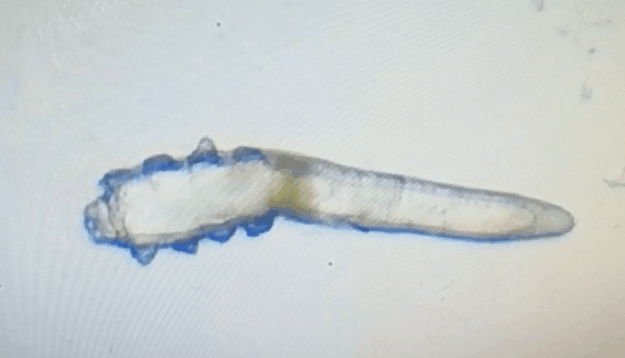

廈門(mén)眼科中心眼表及角膜病專(zhuān)家商旭敏博士指出:蠕形螨中的毛囊蠕形螨和皮脂蠕形螨可寄居于人體。在眼部,毛囊蠕形螨常寄居于睫毛囊,而皮脂蠕形螨多寄居于眼瞼皮膚的皮脂腺和瞼板腺。蠕形螨瞼緣炎是蠕形螨感染瞼緣所致的慢性炎性反應(yīng)性疾病,主要累及瞼緣皮膚、睫毛囊和腺體以及瞼板腺,以眼癢、眼異物感、眼干、瞼緣充血、鱗屑及睫毛根部袖套狀分泌物等為典型臨床表現(xiàn),嚴(yán)重者可引起結(jié)膜及角膜并發(fā)癥,該病可能具有一定的傳染性。

蠕形螨會(huì)引起睫毛異常,引發(fā)瞼緣炎性反應(yīng),瞼板腺堵塞,引起結(jié)膜炎、角膜炎等并發(fā)癥,嚴(yán)重的話(huà)將發(fā)生角膜穿孔致視力損傷甚至失明。